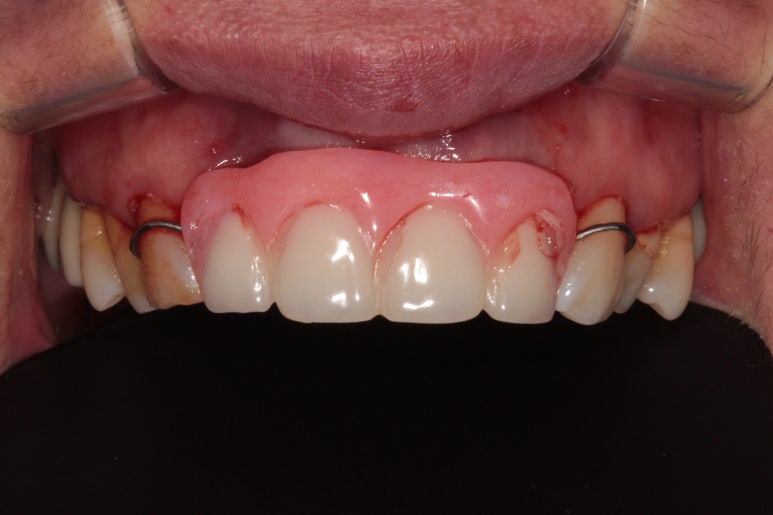

저희 신금호역 치과에서 준비해두었던 앞니 임시틀니를 장착해드렸습니다.

치아가 4개나 없었기 때문에 고정식으로 임시치아를 만들어드리긴 어려웠고, 대신 몇 달만 쓰실 용도로 임시틀니를 끼워드렸어요.

실제로 저작능력은 거의 없습니다만, 사회생활을 하셔야하기에 보이는 용도로써 사용했지요.

실밥제거를 하였습니다.

아직도 아파보이셔서 속상합니다. ㅠㅠ

실밥제거를 하고 보니 잇몸 색은 많이 돌아온 것을 볼 수 있었어요. 정상치유과정을 거치고 있습니다.

하얗게 보이는 것이 위에서 소개했던 비흡수성 차폐막 cytoplast입니다.